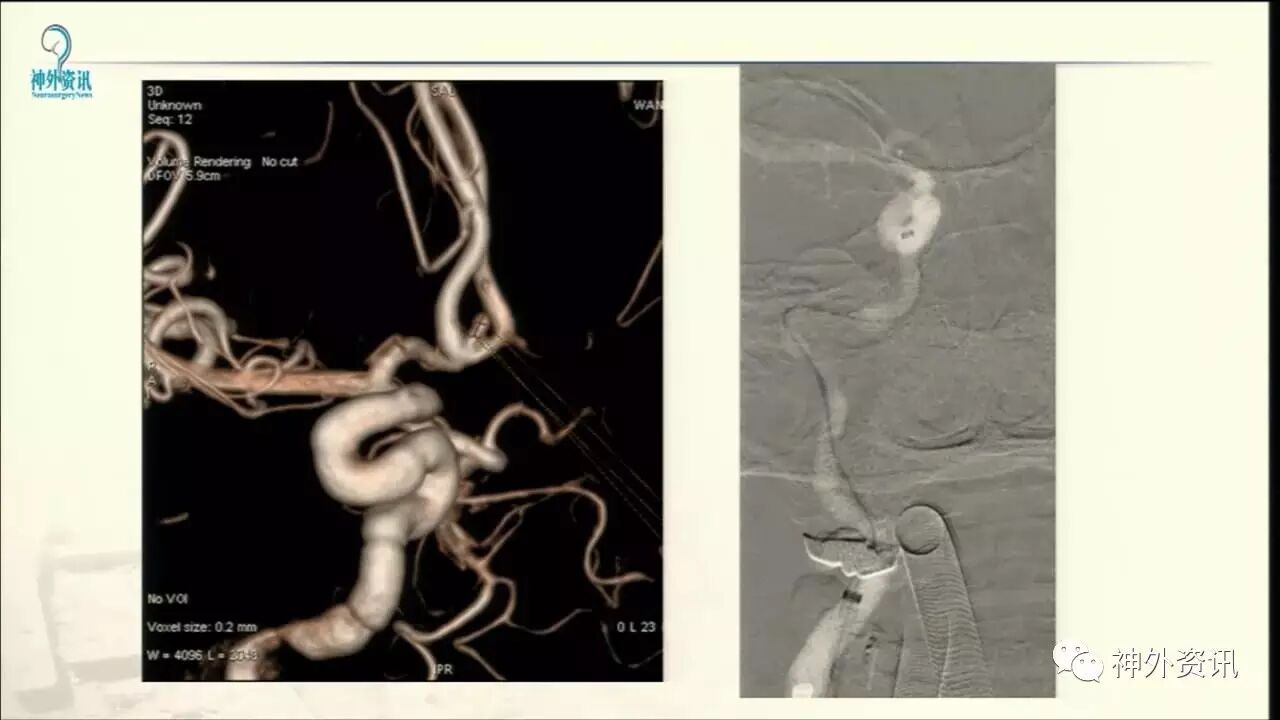

今天“神经介入专栏”为大家分享由上海交通大学医学院附属仁济医院神经外科副主任万杰清教授带来的“颅内小动脉瘤的介入治疗--GALAXY微弹簧圈是一种不错的选择”精彩讲课视频及PPT,欢迎观看、阅读。文章仅代表作者个人观点,如有不同见解,欢迎同道斧正!